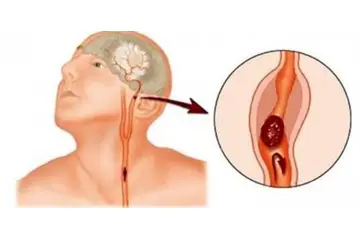

Beyin Dokusunun Sağlık Üzerindeki Etkileri Beyin dokusunun sağlıklı bir şekilde işlev görmesi, genel sağlık üzerinde büyük etkiye sahiptir. Beyin dokusundaki hasar veya bozulmalar, birçok nörolojik hastalığın temelini oluşturur. Öne çıkan sağlık sorunları arasında: